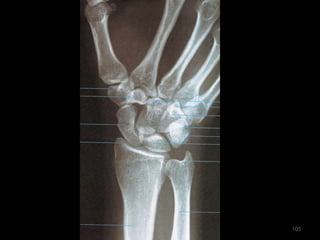

Incidência punho desvio (flexão) ulnar (escafóide) ou incidência  p/ escafóide103

104

105

Incidência punho desvio (flexão) radial- PA de punho106